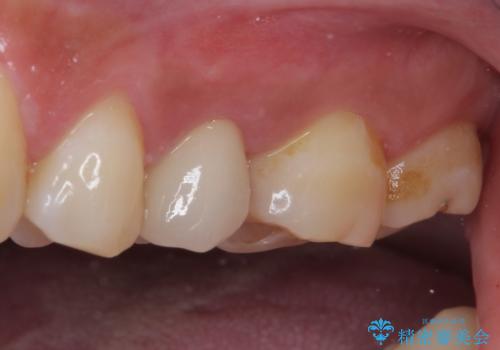

- 上下の歯が接触する度に痛みを感じるとのことで来院された患者様です。

診査の結果、既に歯の神経は失活しており、レントゲンより根尖部に病変を認めました。

根管治療を行った後にオールセラミッククラウンにて補綴することとしました。